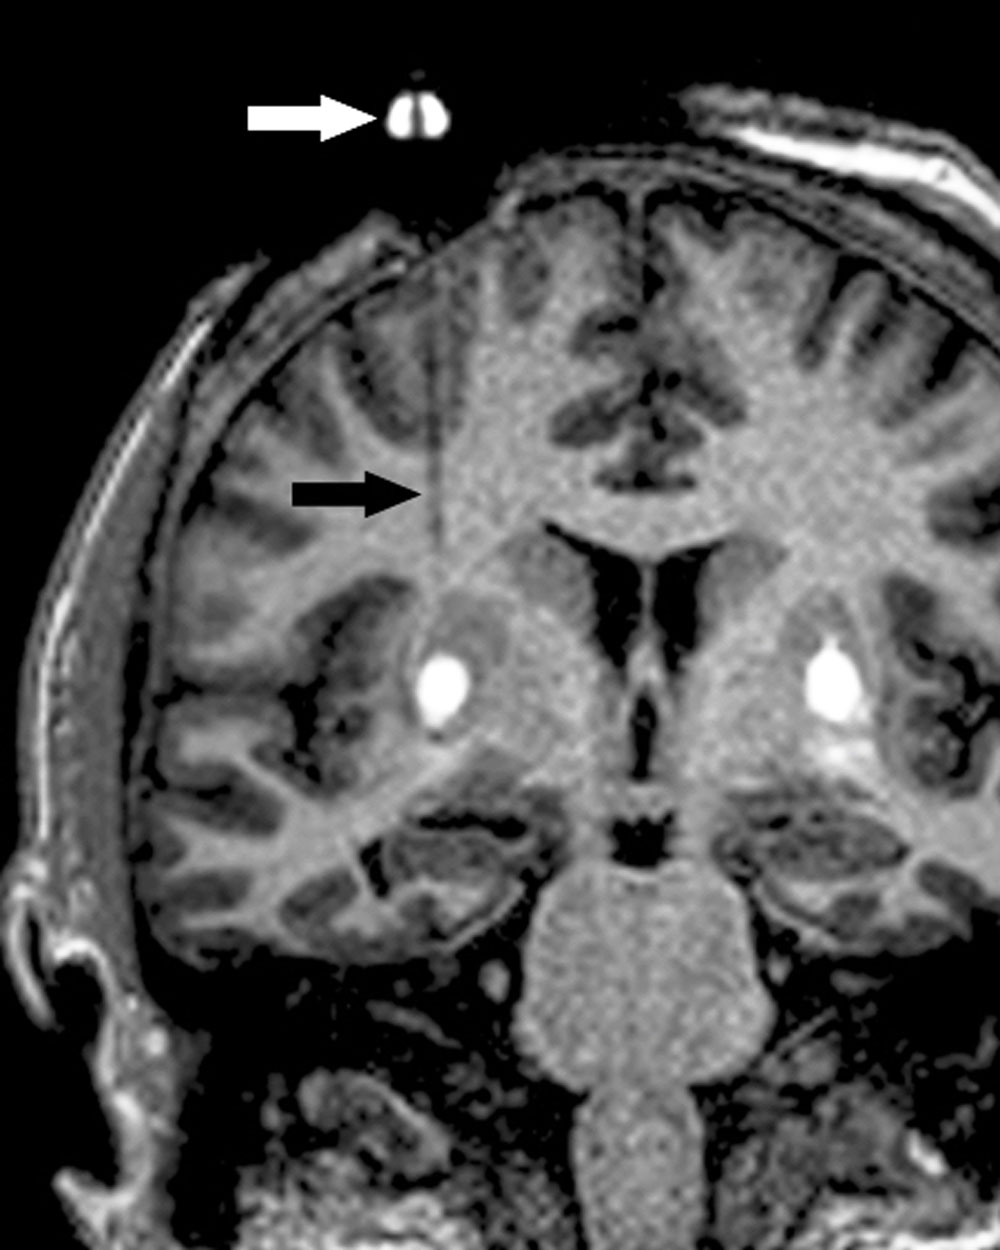

“This is the first gene therapy trial for Parkinson’s disease trial in which intra-operative MRI-guided monitoring was used,” noted first author Chad Christine, MD, of the UCSF Department of Neurology and the Weill Institute for Neurosciences. “This allowed us to visualize and guide the infusion of the treatment into the brain in real time, to ensure delivery to the area that should provide maximum benefit.”

This gradual loss of levodopa’s effectiveness is attributed to AADC, the primary enzyme that converts levodopa to dopamine, which declines as the disease runs its course. Bankiewicz’ group has pioneered the use of gene therapy to address the dwindling supply of this crucial enzyme by delivering the gene for AADC, using an inactive virus. The gene is infused using a catheter into a deep brain structure called the putamen through small holes in the skull.